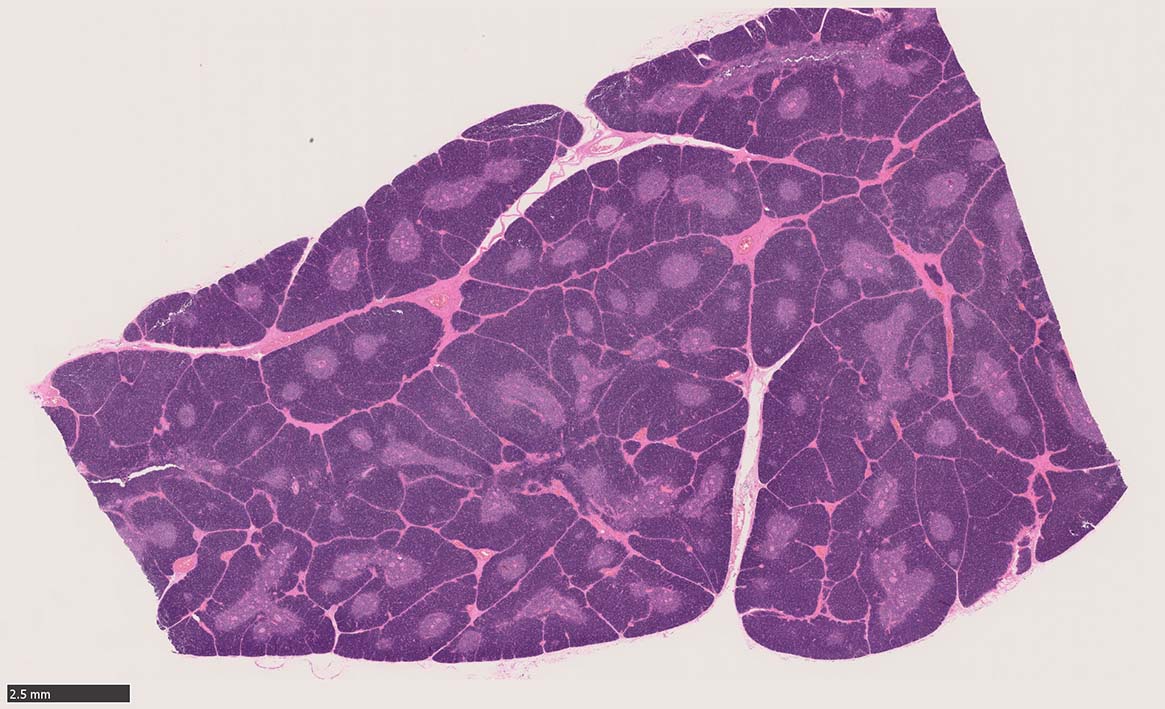

Thymus: 1 year-old boy

1歳男児. 剖検例